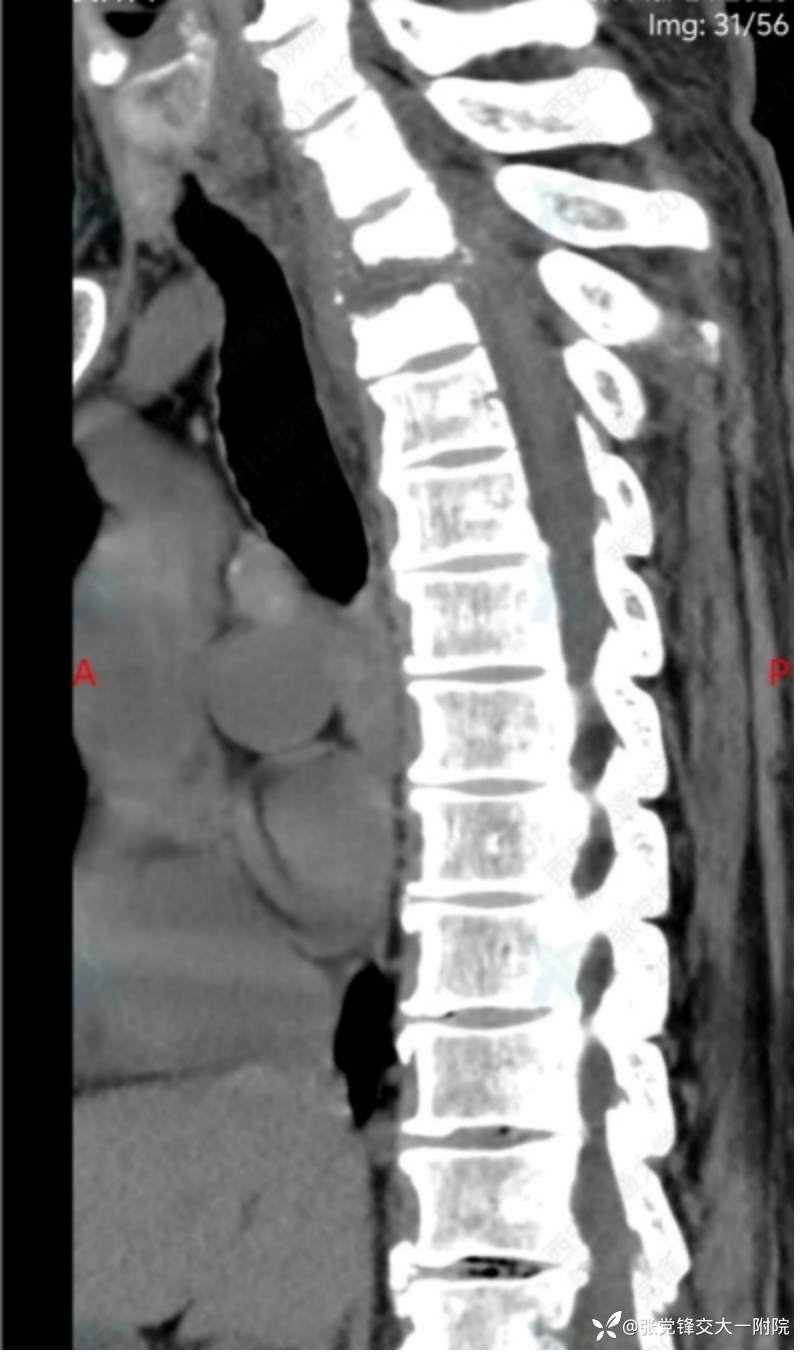

【影像学检查】

术前MRI

术前CT

全身骨显像:胸2-3椎体骨代谢增高,结合病史考虑脊柱结核可能。

1.胸椎结核并不全瘫;2.胸椎管狭窄并脊髓损伤;3.高血压;4.2型糖尿病